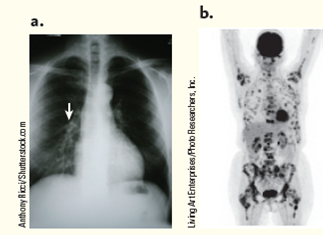

Your aunt tells you that she has just been diagnosed with lung cancer. The oncologist has two images: a chest X-ray film showing a tumor in the left lung (arrow) and a PET scan, which highlights specific areas (in black) where tumors are located ( Fig. ). Considering surgery, radiation therapy, and chemotherapy, what treatment option would you recommend to your aunt given the information you have? Choose any of these treatments that you believe apply and provide support for your choice(s).

Figure Lung cancer test results. (a) X-ray film. (b) PET scan.